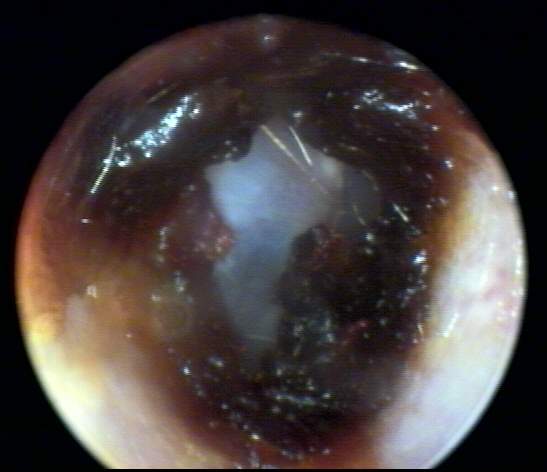

+2: Non-occlusive moderate amount present; likely to interfere with probe tube and ear-insert transducer measurements, hearing aid use, to dimensionally distort or inhibit impression-taking with the possibility of subsequent impaction. Tympanic membrane view may be partially obscured. Removal advised. EXAMPLES:+2/A(25k) | +2/B(23k) | +2/C(21k) | +2/D(21k)